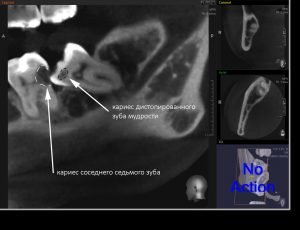

С дистопированными зубами мудрости всё, вроде как, тоже понятно — ввиду их расположения, затрудняется гигиена полости рта, и эти зубы довольно быстро поражаются кариесом. Бывает хуже, если кариес распространяется на соседние семерки, которые, в отличие от восьмёрок, в функциональном отношении весьма важны. Нередко кариес появляется на самой дальней и плохо обозримой поверхности зуба. И человек замечает его лишь тогда, когда всё это дело начинает болеть. То есть, слишком поздно.

Из-за отсутствия костной перегородки между лунками седьмого и восьмого зубов, между ними формируется глубокий карман, куда могут попадать остатки пищи, зубной налёт и микробы, что приводит к воспалению. Иногда довольно острому и опасному для здоровья.